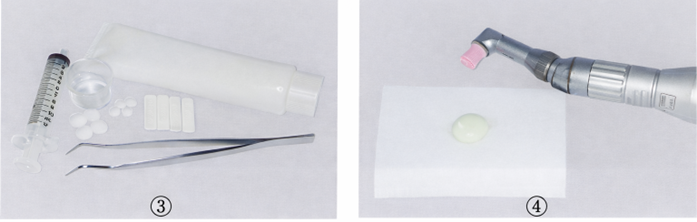

75歳の男性。慢性歯周炎に対する歯周基本治療終了後、3か月間隔で歯周病のメインテナンスと初期の根面う蝕の管理としてフッ化物歯面塗布を行っている。来院時、歯周ポケットの検査を行った後に用いる器材の写真を別に示す。 3番目に用いるのはどれか。1つ選べ。

a. ①

b. ②

c. ③

d. ④

解答を見る

d